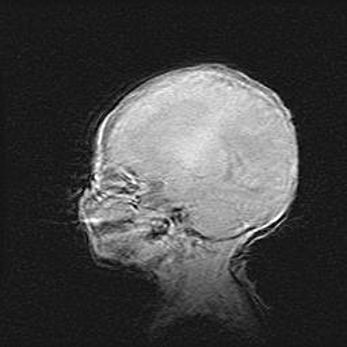

Церебральная ишемия II.

Возраст: 5 дней

Вес: 3400 г

Пол: женский

Окружность головы: 35 см

Срок гестации: 39 недель

Церебральная ишемия – это заболевание, характеризующееся недостаточностью (гипоксией) либо полным прекращением (аноксией) снабжения мозга кислородом по причине закупорки одного или нескольких сосудов. Это приводит к  что метаболическим расстройствам различной степени тяжести в тканях головного мозга, развитию коагуляционных некрозов и гибели нейронов.